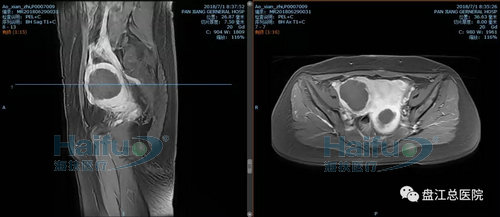

我院案例1:患者敖XX,44岁,多发性子宫肌瘤患者。

因经期延长1+月,发现盆腔包块12+天入院。患者于2018-6-29在我院行高强度聚焦超声消融治疗(HIFU)。在镇静镇痛状态下,治疗过程中未诉有特殊不适,安静休息。本次治疗时间70min。

术前后壁及右侧壁肌瘤增强,见病灶明显强化

术后后壁及右侧壁肌瘤增强,见病灶内已无强化,病灶发生凝固性坏死